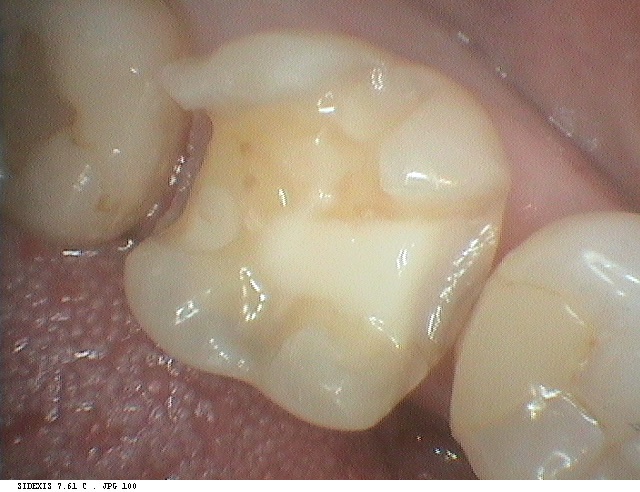

今回の症例の患者さまは左下の奥歯がまさしくその状態でした。

レントゲンを撮影すると欠けた左下6番の歯のみならず、その奥の左下7番目の歯にも、歯と歯の間に虫歯が認められます。

左下6番のコンポジットレジンを除去し、7番目の歯の隣接面う蝕(虫歯)はよく見える状況でコンポジットレジン修復を行いました。